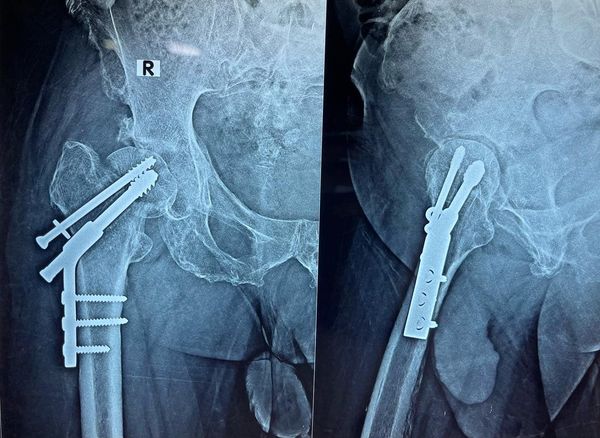

68 year old man ACL (anterior cruciate ligament) reconstruction of Knee

There used to be a common consensus that ACL reconstruction of knee should not be done in old age, this idea has now largely been debunked with statistical evidence. this 68 year old man with a traumatic anterior cruciate ligament tear had intact lateral and medial meniscus and quite normal cartilage in the weight bearing […]